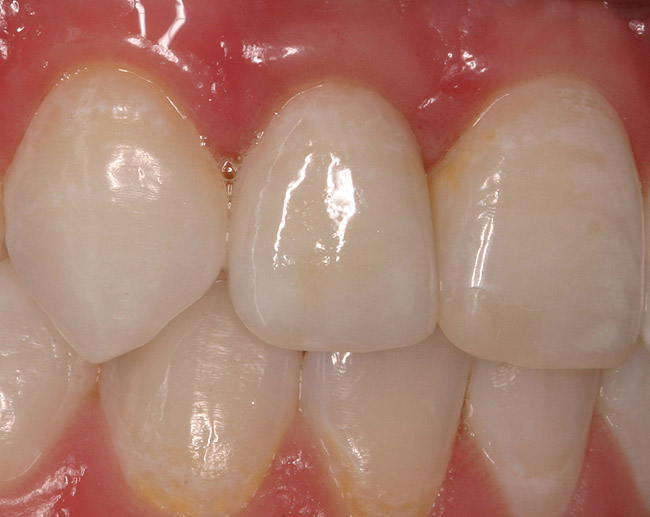

Figure 5d  Completed, porcelain-fused-to-gold implant restorations, custom gold abutments, lingual-set screw-retention, Kerr Extrude¬Æ light-body crown-abutment seal.

Figure 5d

Figure 5e  Completed, porcelain-fused-to-gold implant restorations, custom gold abutments, lingual-set screw-retention, Kerr Extrude¬Æ light-body crown-abutment seal.

Figure 5e

Figure 5f  Completed, porcelain-fused-to-gold implant restorations, custom gold abutments, lingual-set screw-retention, Kerr Extrude¬Æ light-body crown-abutment seal.

Figure 5f